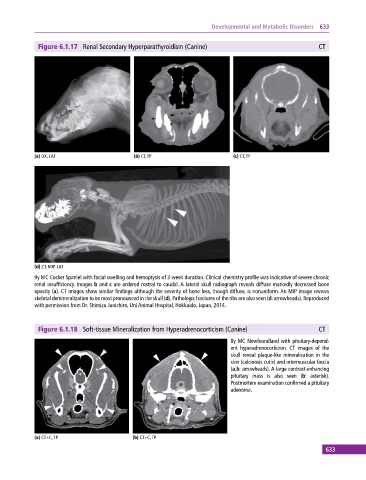

Figure 6.1.17 Renal Secondary Hyperparathyroidism (Canine) CT

(a) DX, LAT (b) CT, TP (c) CT, TP

(d) CT, MIP, LAT

9y MC Cocker Spaniel with facial swelling and hemoptysis of 3‐week duration. Clinical chemistry profile was indicative of severe chronic

renal insufficiency. Images b and c are ordered rostral to caudal. A lateral skull radiograph reveals diffuse markedly decreased bone

opacity (a). CT images show similar findings although the severity of bone loss, though diffuse, is nonuniform. An MIP image reveals

skeletal demineralization to be most pronounced in the skull (d). Pathologic fractures of the ribs are also seen (d: arrowheads). Reproduced

with permission from Dr. Shimizu Junichiro, Uni Animal Hospital, Hokkaido, Japan, 2014.

Figure 6.1.18 Soft‐tissue Mineralization from Hyperadrenocorticism (Canine) CT

8y MC Newfoundland with pituitary‐depend

ent hyperadrenocorticism. CT images of the

skull reveal plaque‐like mineralization in the

skin (calcinosis cutis) and intermuscular fascia

(a,b: arrowheads). A large contrast‐enhancing

pituitary mass is also seen (b: asterisk).

Postmortem examination confirmed a pituitary

adenoma.

(a) CT+C, TP (b) CT+C, TP